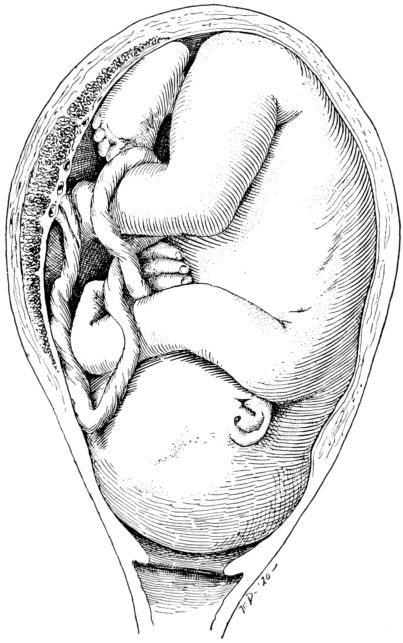

| 50. | Attitude of fetus in uterus at term | 217 |

| 52. | Attitude of fetus in breach presentation | 219 |

| 53. | Attitude of fetus in vertex presentation | 220 |